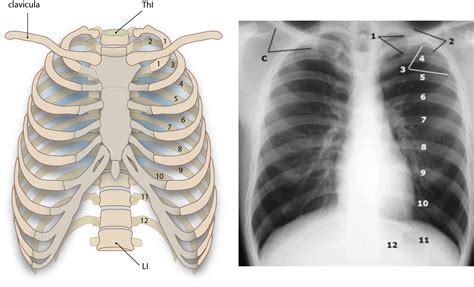

Let’s get down to the nitty-gritty of the os clavicula ’s anatomy, guys. The collarbone is a slender, S-shaped bone that sits right on top of your rib cage, just beneath your skin. It’s one of the most frequently fractured bones in the body, especially in active individuals, so knowing its structure is key. It has two main ends: the sternal end and the acromial end . The sternal end, the medial part, connects to the manubrium of the sternum (your breastbone) at the sternoclavicular joint. This joint is pretty special because it’s one of the few places where a long bone articulates with the axial skeleton. The acromial end, the lateral part, connects to the acromion, which is part of the scapula (your shoulder blade), forming the acromioclavicular (AC) joint. This connection is vital for shoulder girdle mobility.

What does a fractured os clavicula look like? You’ll usually feel intense pain right at the site of the break. You might notice a visible bump or deformity over the collarbone, and the shoulder on the injured side might sag downwards and forwards. It can be really hard to lift your arm, and any attempt to move the shoulder or arm will likely be agonizing. You might also hear or feel a crack or grinding sensation at the time of the injury. It’s super important not to ignore these signs and to seek medical attention immediately if you suspect a collarbone fracture. An X-ray is usually needed to confirm the diagnosis and determine the exact location and severity of the break.